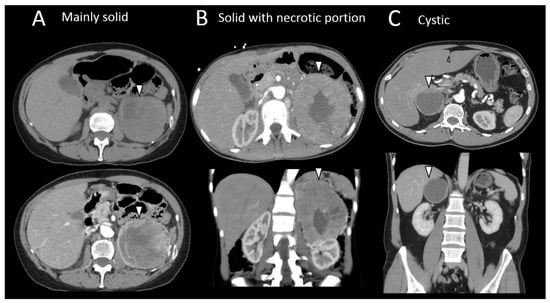

3.4. Pheochromocytomas and Paragangliomas: Variable Morphological Characteristics Using Anatomical Imaging